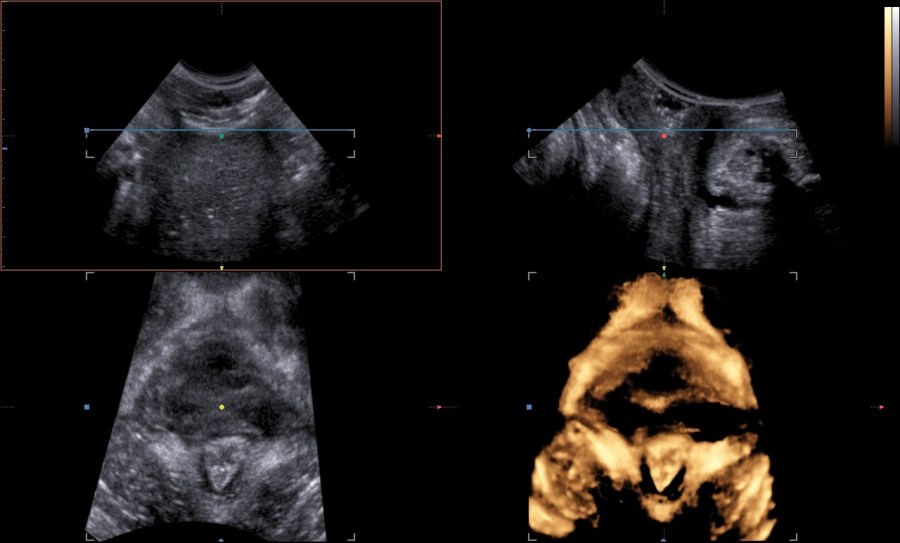

An 80-year-old female patient presents with persisting overactive bladder symptoms. After careful ultrasound examination, a unilocular cystic mass with a single urethral connecting tract containing a calculus was identified as an urethral diverticulum.

The clinician’s suspicion after acquiring a thorough patient’s history should lead to a targetted ultrasound examination combined with digital compression for possible excretion of fluid. The diagnostics may be completed with cystourethroscopy, micturating cystourethrogram, or MRI.